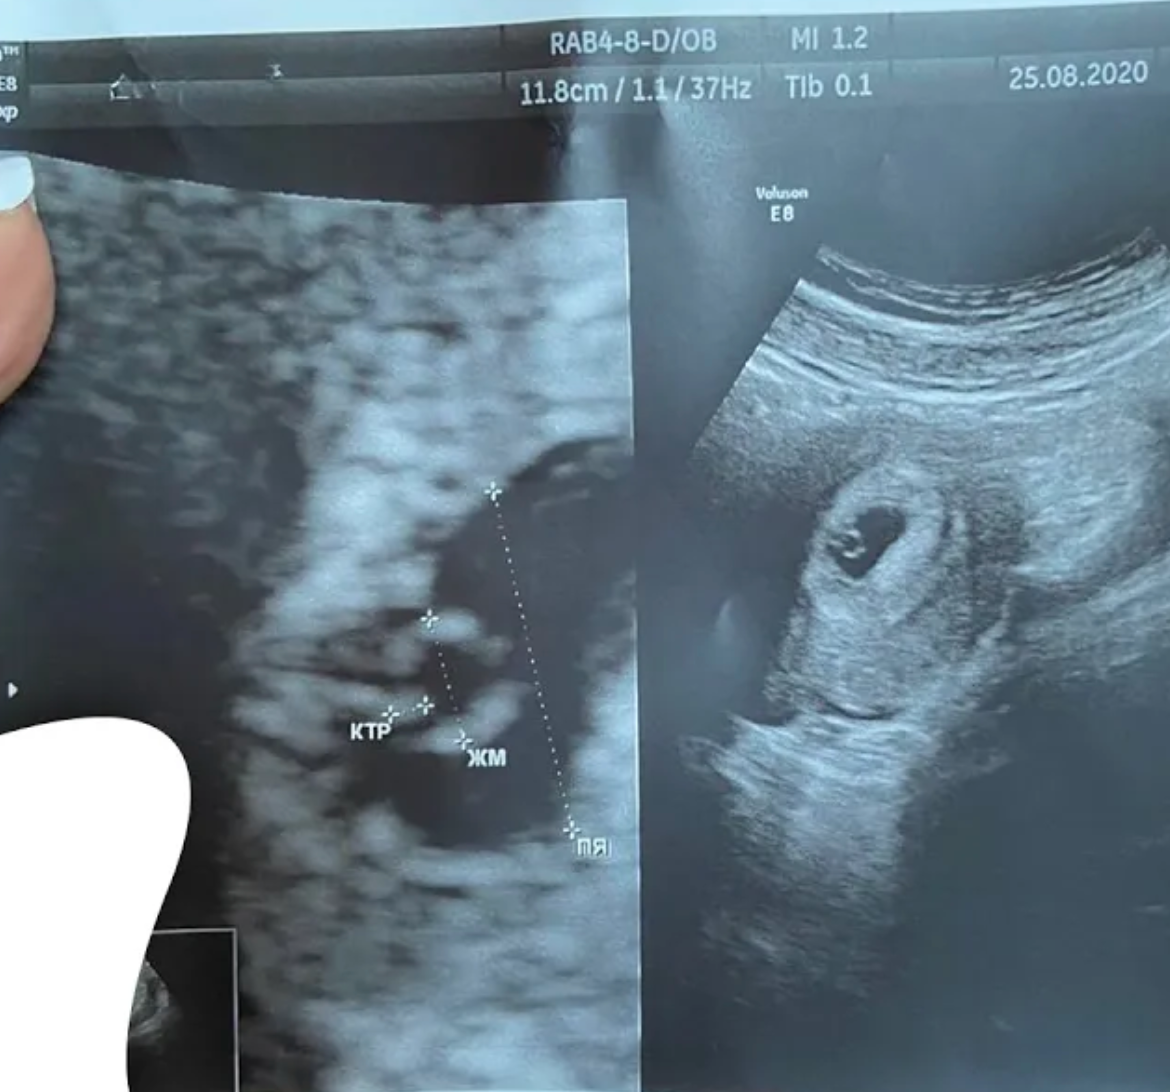

Сонячне Закарпаття. До мене на прийом прийшла жінка 35 років із дуже довгим і непростим шляхом 15 років безпліддя. Основною причиною був чоловічий фактор криптозооспермія. В анамнезі негативний досвід ЕКЗ в іншій клініці: отримано 5 ембріонів, проведено 3 ембріотрансфери, але жоден з них не завершився настанням вагітності.…